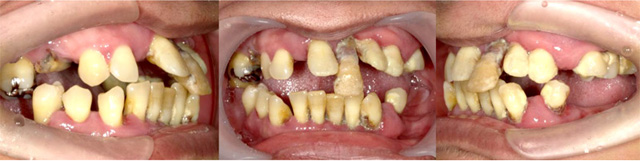

オールオン4の治療例:1

治療前

治療後

オールオン4の治療例:2

その他 ボロボロ虫歯の症例